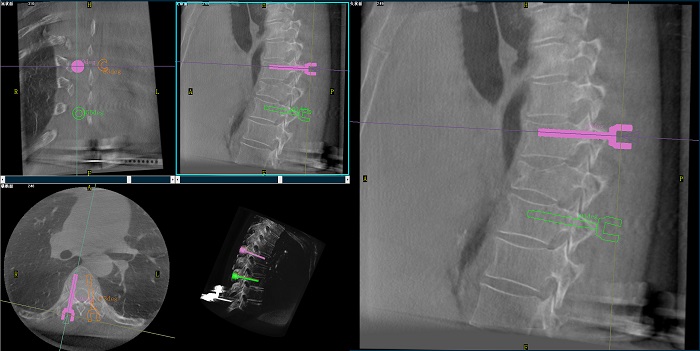

②機器人輔助胸椎手術操作難點之路徑規劃

人體胸椎的椎弓根較腰椎更狹窄,周圍有重要的神經和血管,選擇合適尺寸和長度的螺釘至關重要。螺釘過粗可能損傷椎弓根,過細容易發生形變,固定強度不夠;螺釘過長可能穿透椎體前緣,造成損傷,過短則固定不牢。

普愛醫療手術導航定位系統解決方案

使用機器人輔助手術,醫生不僅可以在影像的引導下,一次性完成多枚螺釘的路徑規劃,提高手術效率,而且可以精確地選擇螺釘的角度、直徑和長度,提高手術的成功率。

機器人做胸椎手術圖像